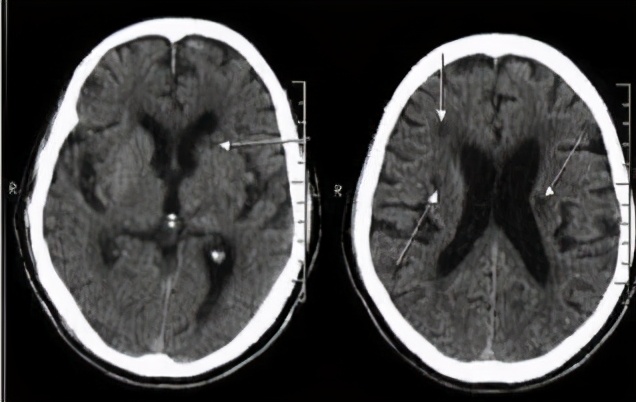

● 在脑梗死中有一种病灶小(2~15mm),症状不明显的梗死,称为腔隙性脑梗死,多是体检偶然做CT或磁共振检查发现的,也称为静止性梗死,这种脑梗死在60岁以上的人较为常见,尤其是患有高血压的人。虽然腔隙性脑梗死早期症状不明显,但是随着病灶的增多和年龄的增长,患者会出现记忆下降或认知功能障碍,甚至平衡障碍。据美国心脏协会(American Heart Association)估计,超过1300万美国人有过一次或多次这种静止性梗死。

多发性脑梗死

● 多发性脑梗死痴呆是因为大脑的多处小血管堵塞,导致脑细胞失去氧气和葡萄糖供给,出现痴呆症状。如果在发生脑梗死的过程中有足够多的神经细胞受损或死亡,记忆就无法恢复了。